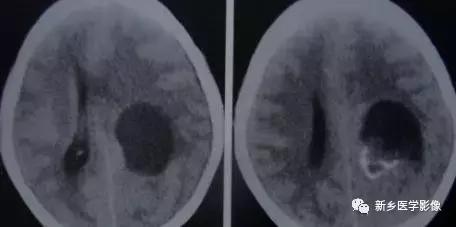

十、结节性硬化

是一种先天性、家族性、遗传性疾病。

临床表现:以皮脂腺瘤、癫痫和智力低下三联征为特征。CT:沿侧脑室边缘对称性排列的钙化结节。